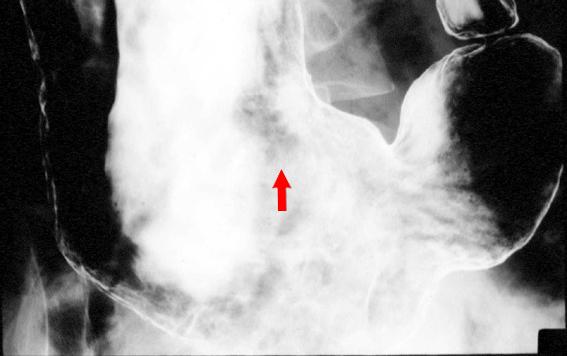

疾病(病理主体)的分类恶性淋巴系统肿瘤/MLP型恶性淋巴瘤

部位(按器官分)胃(部位)/体部

检查方法X线

肿瘤最大直径20~24

多发性肿瘤(同一器官)有(同时性)